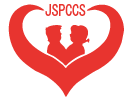

現在11歳の女児で,3歳時に発熱,嘔吐のため前医を受診した際,胸部X線で心拡大を,心エコー検査で心嚢液貯留を認めたため当院に緊急搬送となった.胸部X線で著明な心拡大を認め(Fig. 1a),心電図では広範囲の誘導でST上昇を認めた(Fig. 1b).心臓超音波検査で明らかな疣贅や有意な弁逆流は認めなかったが,大量の心嚢液貯留を認めた(Fig. 1c).呼吸は努力様であり,末梢冷感も著明で,呼びかけにも反応は乏しく心タンポナーデによるショックと診断した.緊急で心嚢ドレナージ術を行い,400 mLの膿性排液を認めた(Fig. 1d).排液の成分は,白血球を認めたが芽球は認めず,糖が2 mg/dLと低値を示し,乳びではなかった.また,心嚢液から化膿性連鎖球菌(Group A Streptococci; GAS)が検出された.インフルエンザウイルスなどの各種ウイルス抗原は全て陰性であり,腹部など他臓器の感染源検索も行ったが異常はなく,GASによる細菌性心膜炎と診断した.その他の原因検索に免疫能も調べたが,抗核抗体などの自己抗体は全て陰性であり,血清補体値や免疫グロブリン値,好中球貪食能や殺菌能などいずれも異常は認めなかった.術後経過は良好で,ガイドラインや過去の報告を参考に,抗生剤点滴加療を2週間行い退院,その後外来で6週間抗生剤内服加療を行った5, 6).